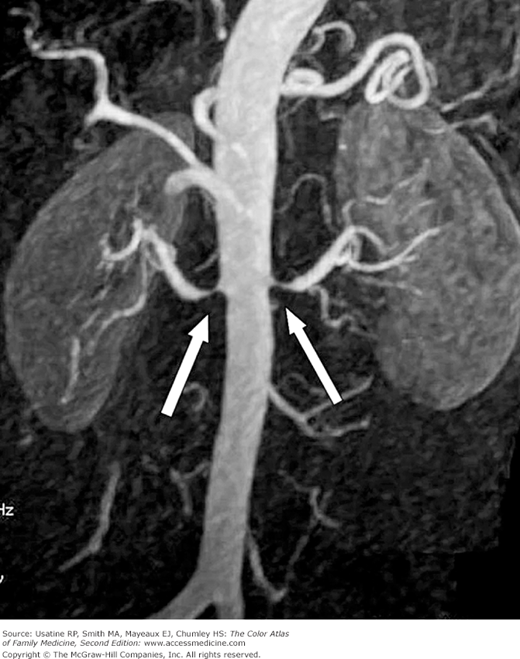

- Secondary HTN (5% to 10% of patients)—Causes include medications, kidney disease, renal artery stenosis (Figure 47-2), thyroid disease, hyperaldosteronism, and sleep apnea. Rare causes include coarctation of the aorta, Cushing syndrome and pheochromocytoma.